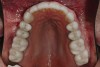

Figure 8  Preoperative view of the upper arch.

Figure 8